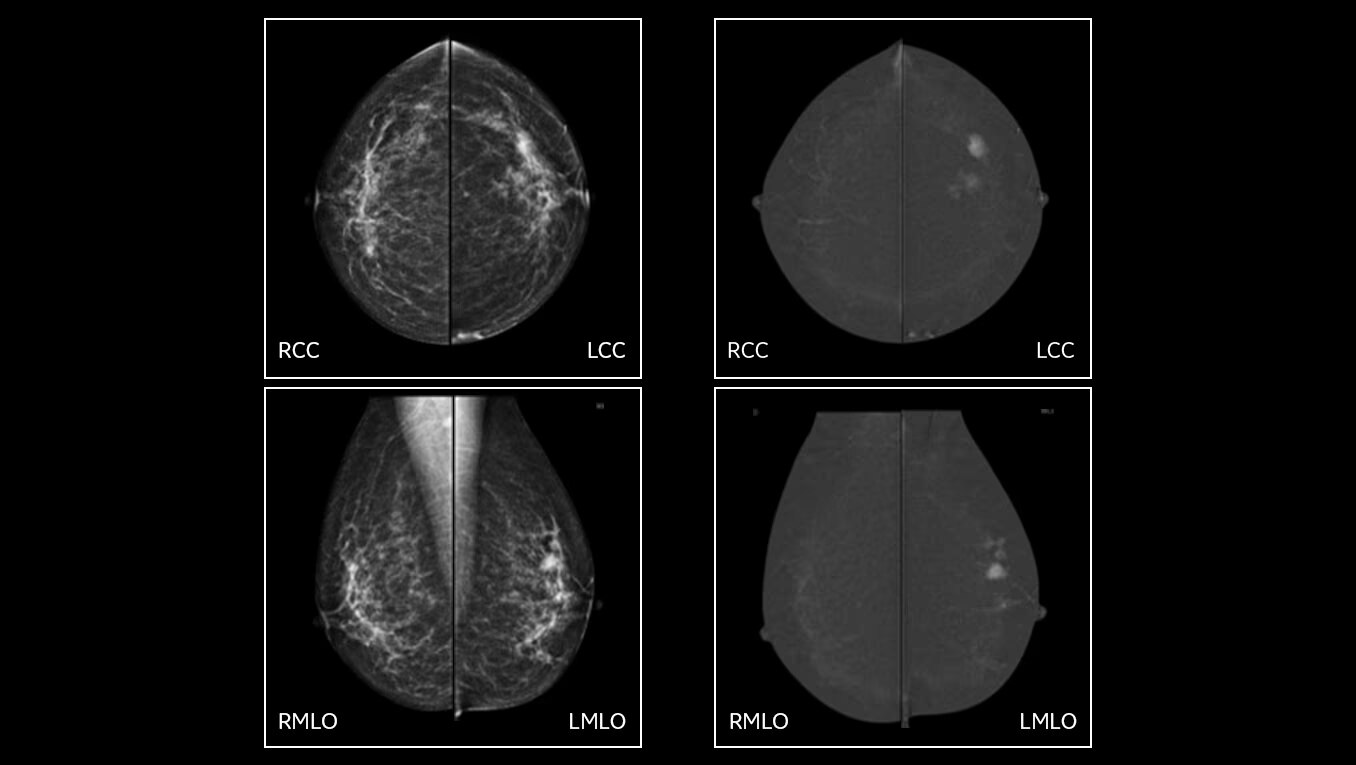

Low dose for diagnostic accuracy

Senographe Pristina is the only FDA approved 3D mammography that delivers at the same low dose as 2D FFDM, the lowest patient dose of all FDA approved systems2. The platform is upgradeable to advanced applications, including contrast-enhanced mammography and biopsy.

Exceptional image quality for diagnostic accuracy

Our engineering teams work passionately to develop solutions designed to achieve exceptional Image quality:

• 2D with eConstrast HD: the new processing improves the reading workflow by reducing the need to manually window our images and the radiologist confidence in our 2D image quality.

• 3D with Asir: reconstruction enables artifact management techniques that greatly reduces propagation of clips/microcalcs, at the expense of extra computation time (Asir is longer than FBP reconstruction.

• CEM with Nira: thanks to the new recombination algorithm, the impact of the artifacts is significantly reduced for all readers and may improve confidence in the diagnosis5.